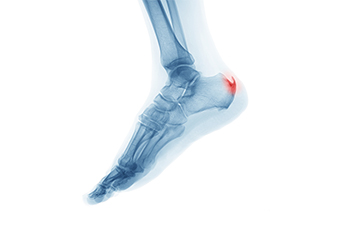

Potential Achilles Tendon Injuries

If you feel the back of your ankle, you will notice the fibrous tissue that connects the heel bone to the calf muscle. This is known as the Achilles tendon. There are two injuries that commonly affect this tendon. The first, known as Achilles tendinopathy, occurs when there is pain on the back of the heel as a result of overuse. Common signs of Achilles tendinopathy include swelling, stiffness, and pain that is worse in the morning. The second injury is an Achilles tendon rupture or tear, which commonly occurs as a result of jumping and pivoting with a lot of force. This causes the tendon to overstretch and eventually tear. Anyone who tears their Achilles tendon will notice a severe pain and a loss of both movement and strength in the tendon. If you are experiencing pain or swelling in your Achilles tendon, it is suggested that you consult with a podiatrist who can help provide a treatment option for injuries as well as ways to prevent a rupture.

What Is the Bump on the Back of My Heel?

Sometimes a bony lump forms on the back of the heel, commonly referred to as a pump bump. It may be caused by the rubbing of your heel on the inside of the shoe. Activity can aggravate the bumps, which normally form on both heels and sometimes lead to pain. Wearing shoes with no heel can increase your comfort level but will not reduce or affect the lump itself. A podiatrist can take an X-ray of the area to determine its severity and suggest non-surgical or surgical treatment options as needed. One such remedy is a change in footwear to a more softly cushioned heel counter, which can help to alleviate any pain or swelling in the area. Further, a heel insert may help alleviate discomfort. If the pump bump continues to enlarge and becomes painful enough to interfere with your daily activities, a podiatrist can also recommend remedies that will help bring relief.

Many people suffer from bouts of heel pain. For more information, contact Roy Moeller, DPM of Foot & Ankle Physicians West. Our doctors can provide the care you need to keep you pain-free and on your feet.

Causes of Heel Pain

Heel pain is often associated with plantar fasciitis. The plantar fascia is a band of tissues that extends along the bottom of the foot. A rip or tear in this ligament can cause inflammation of the tissue.

Achilles tendonitis is another cause of heel pain. Inflammation of the Achilles tendon will cause pain from fractures and muscle tearing. Lack of flexibility is also another symptom.

Heel spurs are another cause of pain. When the tissues of the plantar fascia undergo a great deal of stress, it can lead to ligament separation from the heel bone, causing heel spurs.

Heel pain should be treated as soon as possible for immediate results. Keeping your feet in a stress-free environment will help. If you suffer from Achilles tendonitis or plantar fasciitis, applying ice will reduce the swelling. Stretching before an exercise like running will help the muscles. Using all these tips will help make heel pain a condition of the past.